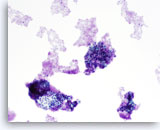

Lubricant A treated vial

…shows the effect of excessive lubricant. Superficial and Intermediate cells are clumped into a three dimensional group. Cells are less evenly dispersed with scant amorphous material noted in the background suggestive of lubricant.

10x

Lubricant A treated vial

…shows the effect of excessive lubricant. Superficial and Intermediate cells are clumped into a three dimensional group. Cells are less evenly dispersed with scant amorphous material noted in the background suggestive of lubricant.

10x